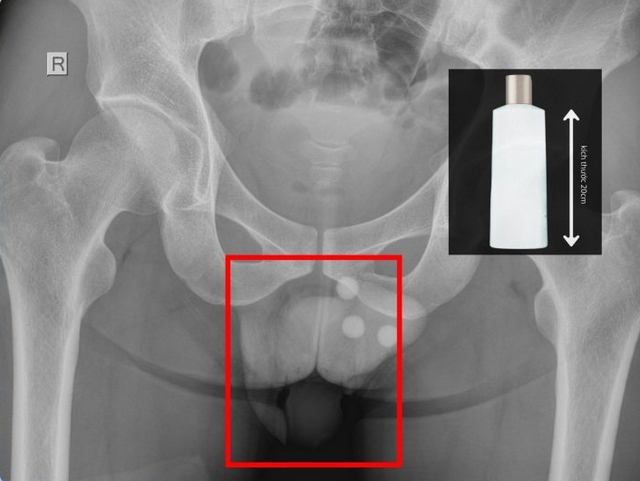

BS.CKII Nguyễn Vũ An – Trưởng khoa Ngoại Tổng quát cho biết, qua thăm khám lâm sàng và chụp X-quang, các bác sĩ xác định có một chai nhựa nằm sâu trong trực tràng, không thể lấy ra bằng các thủ thuật thông thường. Ê-kíp đã tiến hành gây tê tủy sống, nong hậu môn và cẩn trọng lấy dị vật ra ngoài.

Ảnh: BVCC